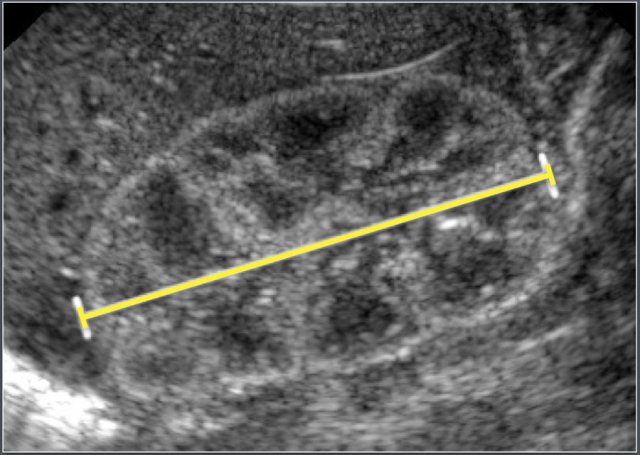

Adapted from an ultrasonographic study of 1483 neonates, gestational age range 25-42 weeks.

The neonates were examinded at day 3.

All neonates with perinatal asphyxia, infection of the central nervous system, intracranial hemorrhages of craniospinal malformation were excluded.

The anterior horn width and the ventriculo-hemspheric ratio is measured on the coronal view at the level of the foramen of Monro.